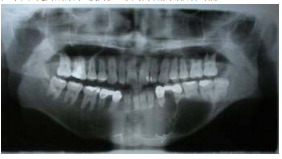

13.如下圖X光片所顯示之影像,下列何者診斷較有可能?

(A)Osteosarcoma (B)Ameloblastoma (C)Dentigerous cyst (D)Median mandibular cyst